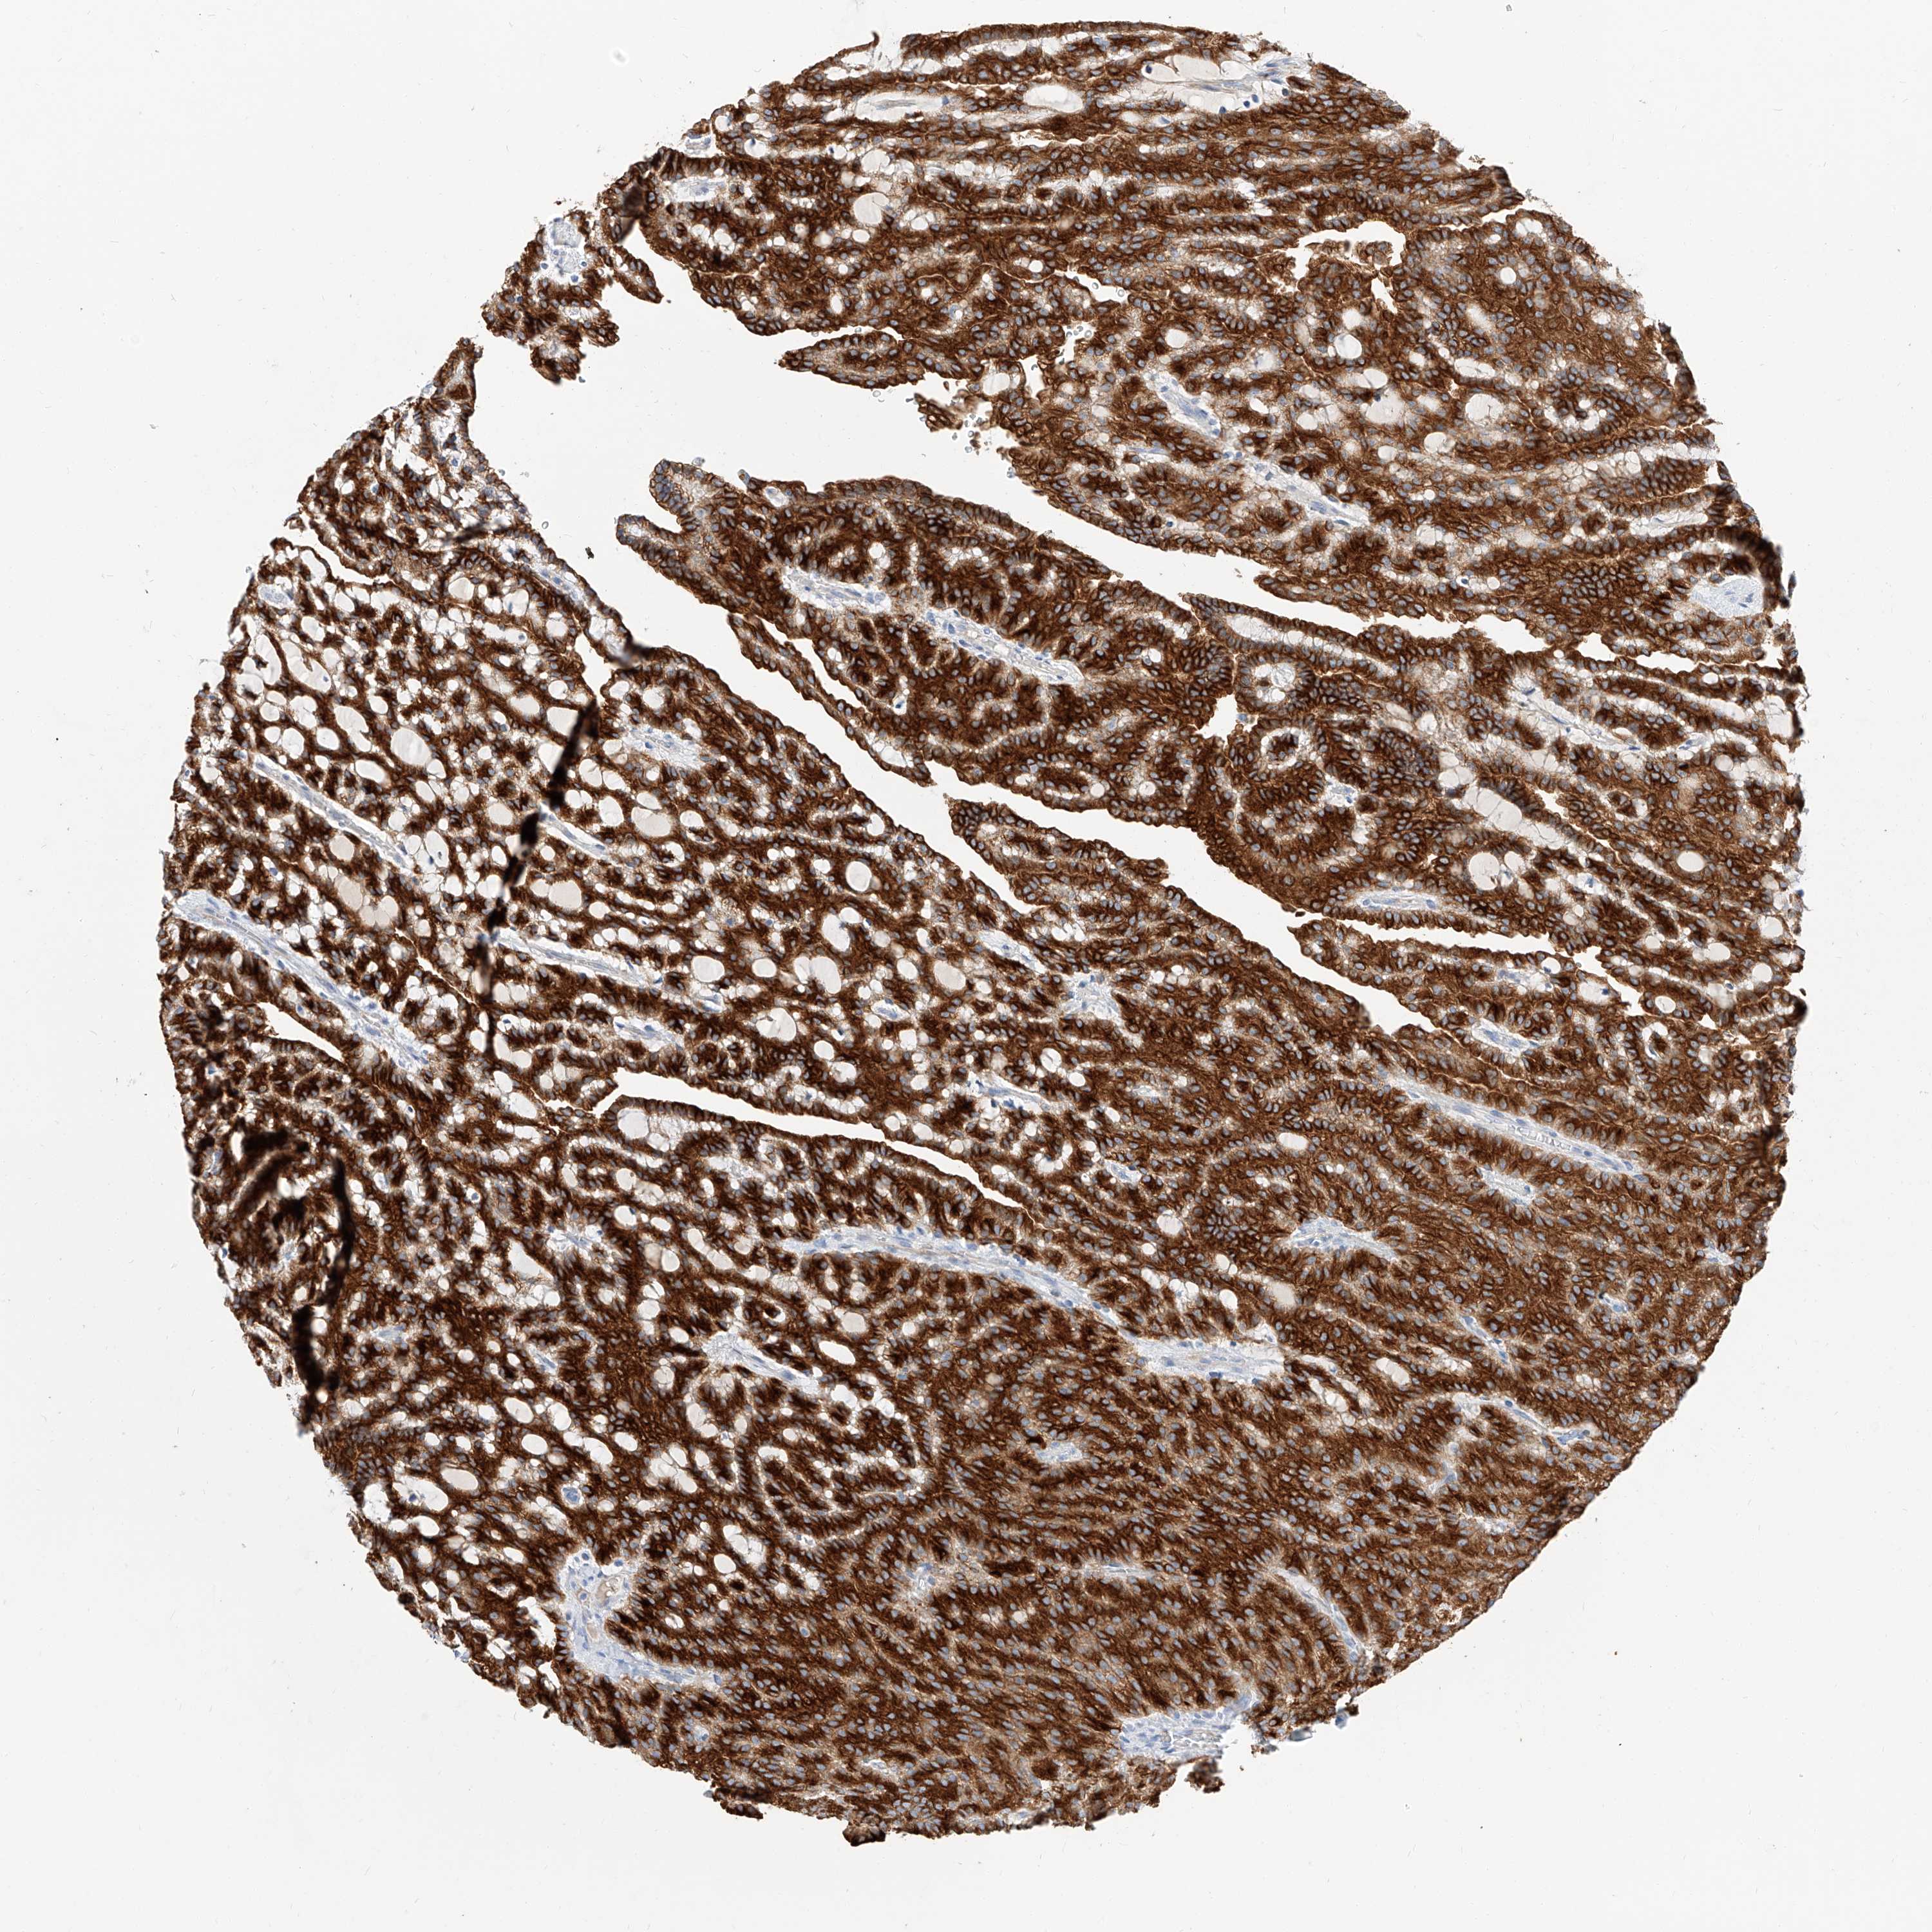

KIDNEY RENAL CLEAR CELL CARCINOMA (TCGA) - Interactive survival scatter ploti

The Survival Scatter plot shows the clinical status (i.e. dead or alive) for all individuals in the patient cohort, based on the same data that underlies the corresponding Kaplan-Meier plots. Patients that are alive at last time for follow-up are shown in blue and patients who have died during the study are shown in red.

The x-axis shows the expression levels (FPKM) of the investigated gene in the tumor tissue at the time of diagnosis. The y-axis shows the follow-up time after diagnosis (years). Both axes are complimented with kernel density curves demonstrating the data density over the axes. The top density plot shows the expression levels (FPKM) distribution among dead (red) and alive patients (blue). The right density plot shows the data density of the survived years of dead patients with high and low expression levels respectively, stratified using the cutoff indicated by the vertical dashed line through the Survival Scatter plot. This cutoff is automatically defined based on the FPKM cutoff that minimizes the p-score. The cutoff can be changed by dragging the vertical line or by entering a cutoff value in the square labeled "Current cut-off".

Under the Survival Scatter plot the p-score landscape (black curve; left axis) is shown together with dead median separation (red curve; right axis). Dead median separation is the difference in median mRNA expression between patients who have died with high and low expression, respectively. It is calculated as follows: median FPKM expression of dead patients with high expression - median FPKM expression of dead patients with low expression. This is intended to aid the user in visually exploring custom cutoffs and the associated p-scores and dead median separation.

Individual patient data is displayed and can be filtered by clicking on one or more of the category buttons on the top of the page. Categories describing expression level and patient information include: high, low, alive, dead, female, male and tumor stages. The scale of the x-axis can be toggled between linear and log-scale by clicking on the "x log" button. Mouse-over function shows TCGA ID, patient information and mRNA expression (FPKM) for each patient.

& Survival analysisi

Kaplan-Meier plots summarize results from analysis of correlation between mRNA expression level and patient survival. Patients were divided based on level of expression into one of the two groups "low" (under cut off) or "high" (over cut off). X-axis shows time for survival (years) and y-axis shows the probability of survival, where 1.0 corresponds to 100 percent.

MAP7 is validated prognostic, high expression is favorable in Kidney Renal Clear Cell Carcinoma (TCGA)

Best expression cut offi

Based on the FPKM value of each gene, patients were classified into two groups and association between prognosis (survival) and gene expression (FPKM) was examined. The best expression cut-off refers the FPKM value that yields maximal difference with regard to survival between the two groups at the lowest log-rank P-value. Best expression cut-off was selected based on survival analysis .

When clicking on this number, the vertical dashed line indicating cut-off, the interactive survival plot, and the Kaplan-Meier curve will be adjusted to show results based on the best expression cut-off.

: 9.36

TCGA RNA samplesi

RNA-seq data is reported as average FPKM (number Fragments Per Kilobase of exon per Million reads), generated by the The Cancer Genome Atlas (TCGA) .

Normal distribution across the dataset is visualized with box plots, shown as median and 25th and 75th percentiles. Points are displayed as outliers if they are above or below 1.5 times the interquartile range. FPKM values of the individual samples are presented next to the box plot.

Average pTPM 23.2

Number of samples 521